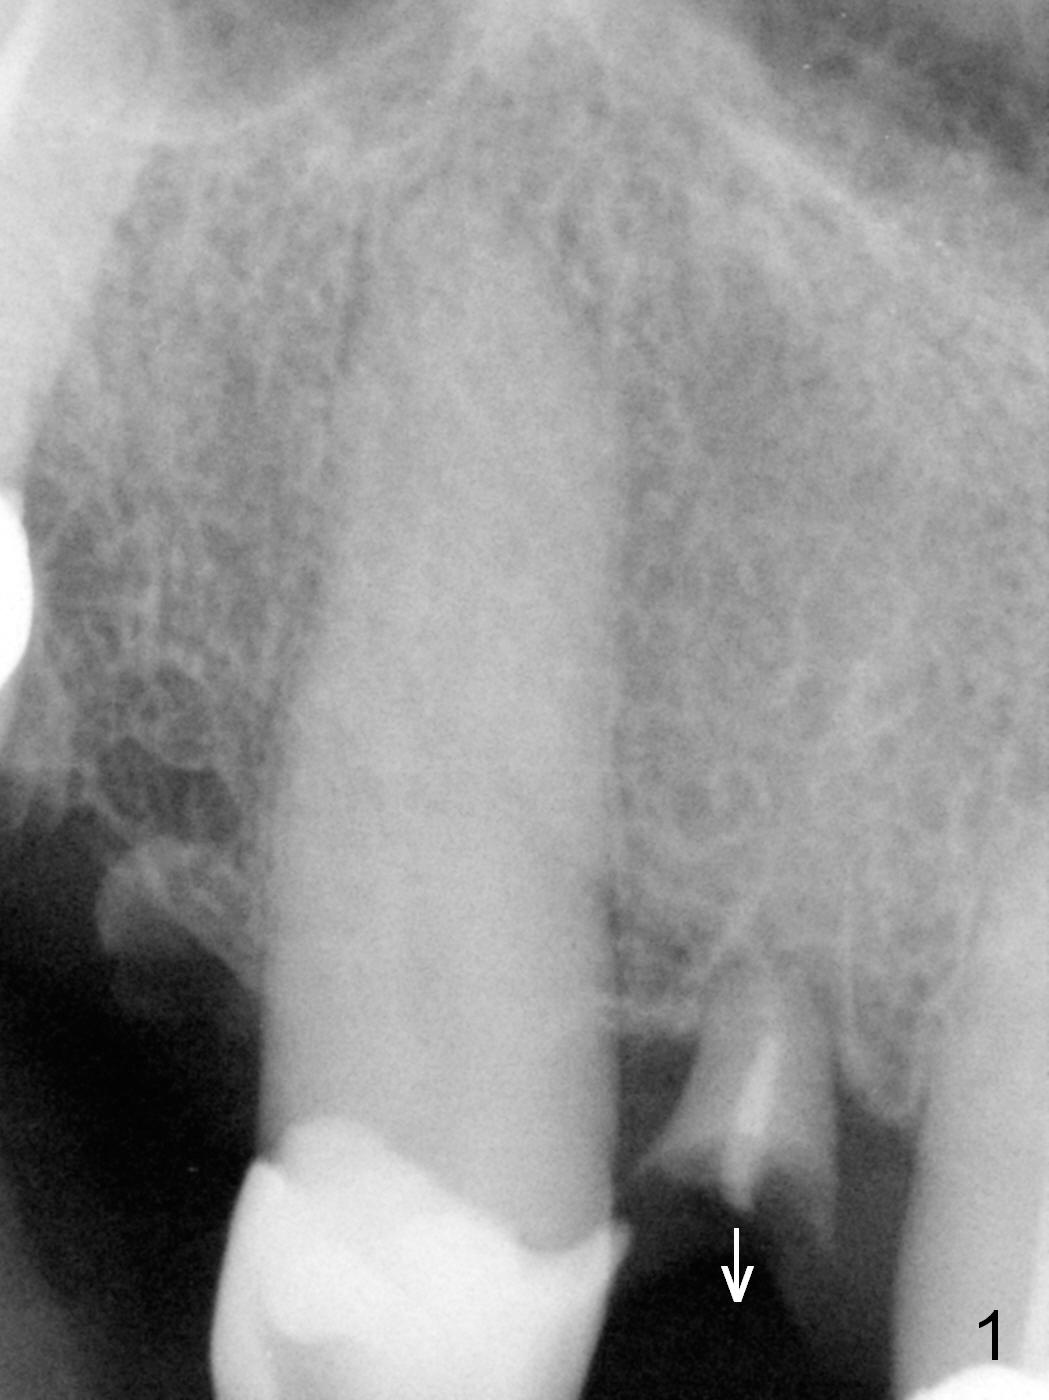

A 59-year-old man (used to be coke drinker) has several missing teeth and residual roots. He wants to get rid of a loose flipper for #7, which is incisally (Fig.1 arrow) and labially (take preop photos) displaced. When it is extracted with curettage of apical granulation tissue (Clindamycin), the socket may not be completely exposed, especially palatally. Do not hesitate to make incision for better visibility and precise osteotomy. If the mesiodistal width of the edentulous space is more than 6.4 mm (Fig.2), use 1.6 mm pilot drill. Otherwise consider 1-piece implant. Pay attention to bone density while drilling. The initial depth will be 10 or 11 mm. PA is to be taken for trajectory and depth confirmation. To prevent periimplantitis, make sure that the first coronal thread is below the labial crest. Due to several missing teeth with insufficient posterior support, the immediate provisional should have daylight clearance. CT shows that 3.8 mm wide implant is appropriate for the buccopalatal width (Fig.3). Retrospectively, the implant could be smaller or to be placed more palatal. If the bone density is low, the implant could be longer than 13 mm.